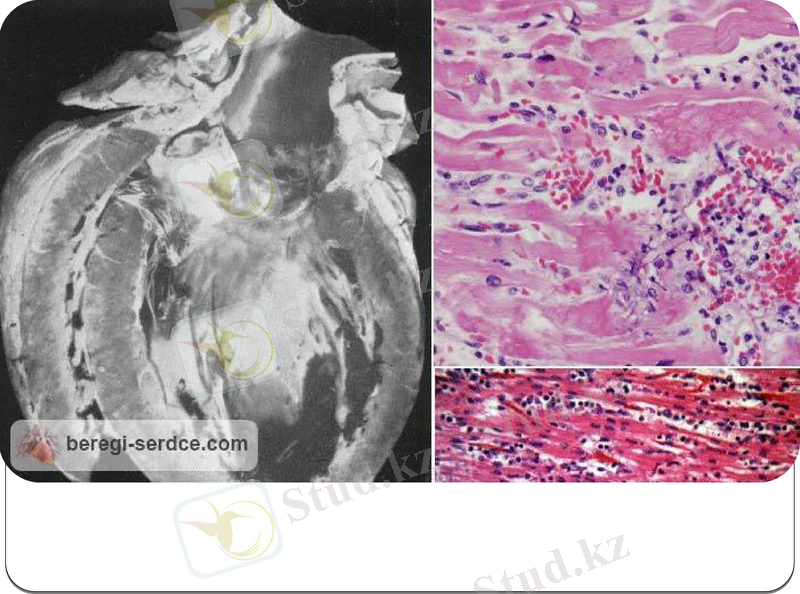

Патологоанатомиялық зерттеу уақытында жүректің айтарлықтай ұлғайғанын көреміз.

Екіншілік эндокардиалды фиброэластоз кезінде сол жақ қарыншаның қуысы кішірейген, ал біріншілік ЭФ-да керісінше күрт кеңею байқалады.

Жүректің сол жақ бөліміндегі эндокардтың фиброэластикалық талшықтары жуандаған. Бұл процесс қақпақшаларға беріледі. (әсіресе митралды және қолқалық)

Микроскоппен қарағанда фиброэластикалық талшықтардағы трабекуляры синусоидтарды көреміз. Бұл процесс дегенеративті өзгерістерді тудырады, кейін қарыншалар миокардының субэндокардиалды аймағындағы бұлшықет қабатының некрозы пайда болады.

Абрамов-Фидлер миокардитінің типтік көрінісі: Жүректің оқшауланған зақымдалуы, кардиосклерозбен тіркескен миокардтың ауқымды дистрофиялық, инфильтративті-қабынулық өзгерістері, жүрекішілік тромб пен үлкен қанайналым шеңберінің эмболиясы.